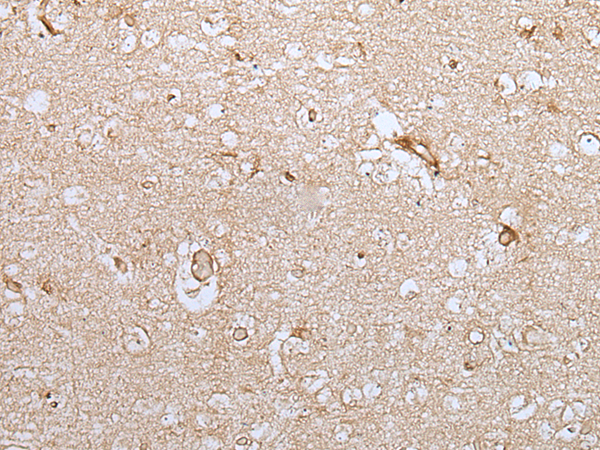

分类: 科研抗体货号: P12721别名: CNP1应用: WB,IHC反应种属: Human, Rat

分类: 科研抗体货号: P12733别名: GAS应用: IHC反应种属: Human, Mouse, Rat